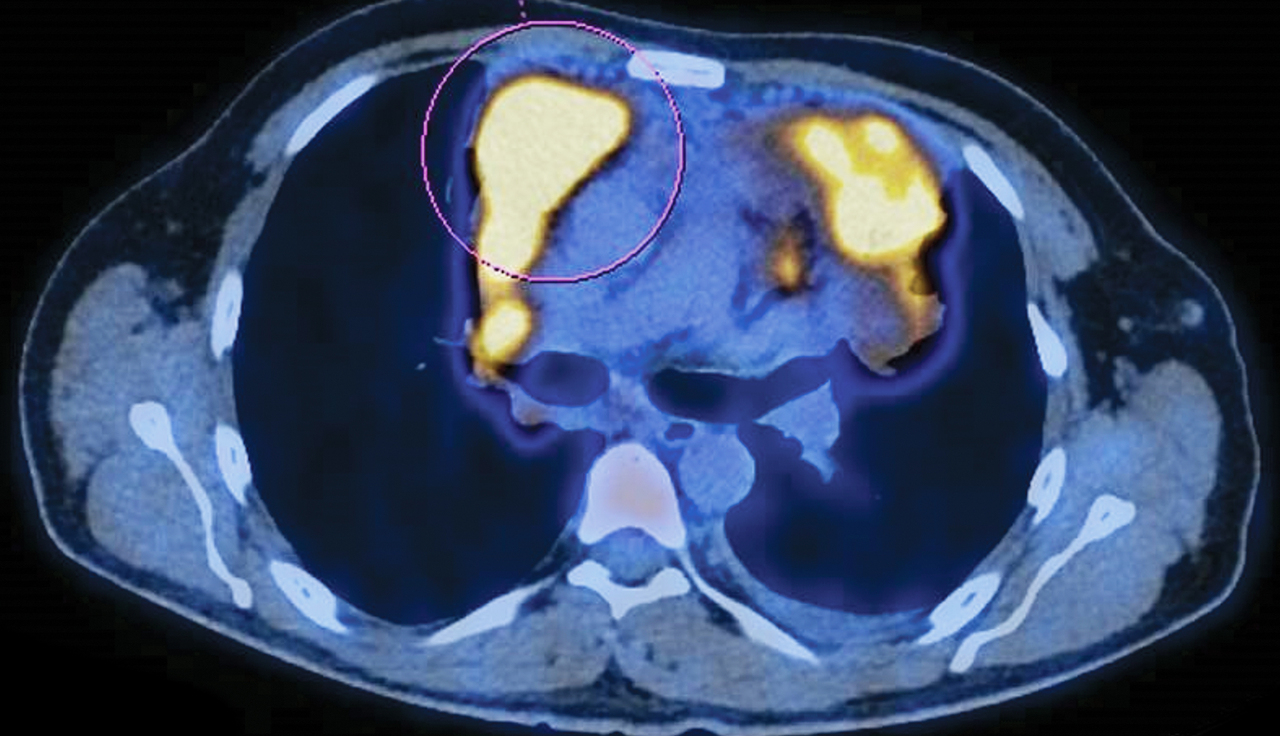

Un homme de 40 ans consulte pour des douleurs thoraciques, une fièvre, des sueurs et une altération de l’état général.

Quel est votre diagnostic ?